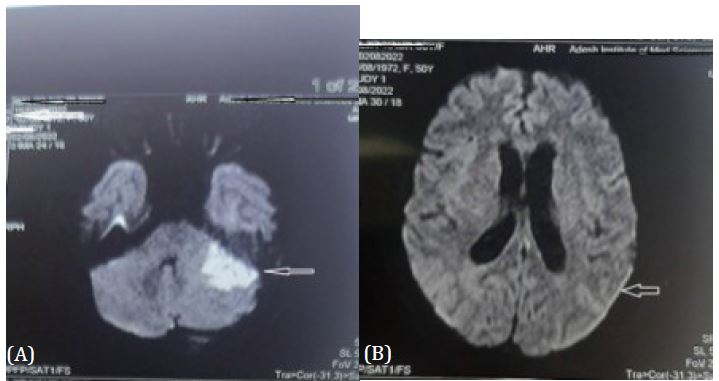

A 50 year female known case of Diabetes Mellitus since 5 years not on any medication presented in emergency with history of fever, altered sensorium and vomiting since one day. She was shifted to ICU. Her Glasgow coma score was 8 (E2V1M5), blood pressure of 130/70 mmHg, heart rate of 110/min and respiratory rate of 24/min. Both pupils were equal in size and normal reaction to light and nuchal rigidity was present. She was intubated due to poor GCS and put on mechanical ventilation. Contrast MRI Brain revealed acute infarct in left middle cerebellar peduncle and left cerebellar hemisphere, periventricular ooze and leptomeningeal enhancement on post contrast FLAIR (Figure 1). Her blood investigations were normal except for leukocytes count of 17500 cells/μL, random blood sugar of 396 and procalcitonin 2.3. Lumbar puncture was done. Cerebrospinal Fluid was turbid yellow and showed protein 274 mg/dl, glucose 23 mg/dl(corresponding blood sugar was 382 mg %) and a total leucocyte count of 280/mm3 (neutrophills - 70%, Lymphocytes – 2%), no organism on gram ZN, Gram staining and KOH prepration. The CSF was also negative for gene expert for Tuberculosis, Polymerase chain reaction for herpes and cryptococcal antigen. She was treated with Monocef and vancomycin after Intravenous dexamethasone, Insulin infusion, intravenous fluids and other supportive treatment. Ear discharge was noted and sent for culture sensitivity. The culture after 24 hours revealed growth of gram-positive organism which later on confirmed to be methicillin resistant Staphylococcus Aureus (MRSA) sensitive to vancomycin. She responded to treatment with normalization of leucocytes and improved her GCS. On day 4, she was conscious oriented to time place and person, weaned from the ventilator and extubated. On day 9th, she was shifted in ward. After 2 weeks of intravenous antibiotlc therapy, she was discharged in stable condition on day 15th.

Figure 1: (A) MRI image Upper arrow showing left cerebellar infarct.

(B) Lower arrow showing leptomeningeal enhancement.

The MRI was done because of altered sensorium and to rule out any features of raised intracranial pressure, as lumbar puncture was to be done for CSF analysis. The MRI was suggestive of left cerebellar infarct with hemorrhagic conversion due to vasculitis and leptomeningeal enhancement on bilateral cerebral hemispheres. CSF revealed acute bacterial meningitis.